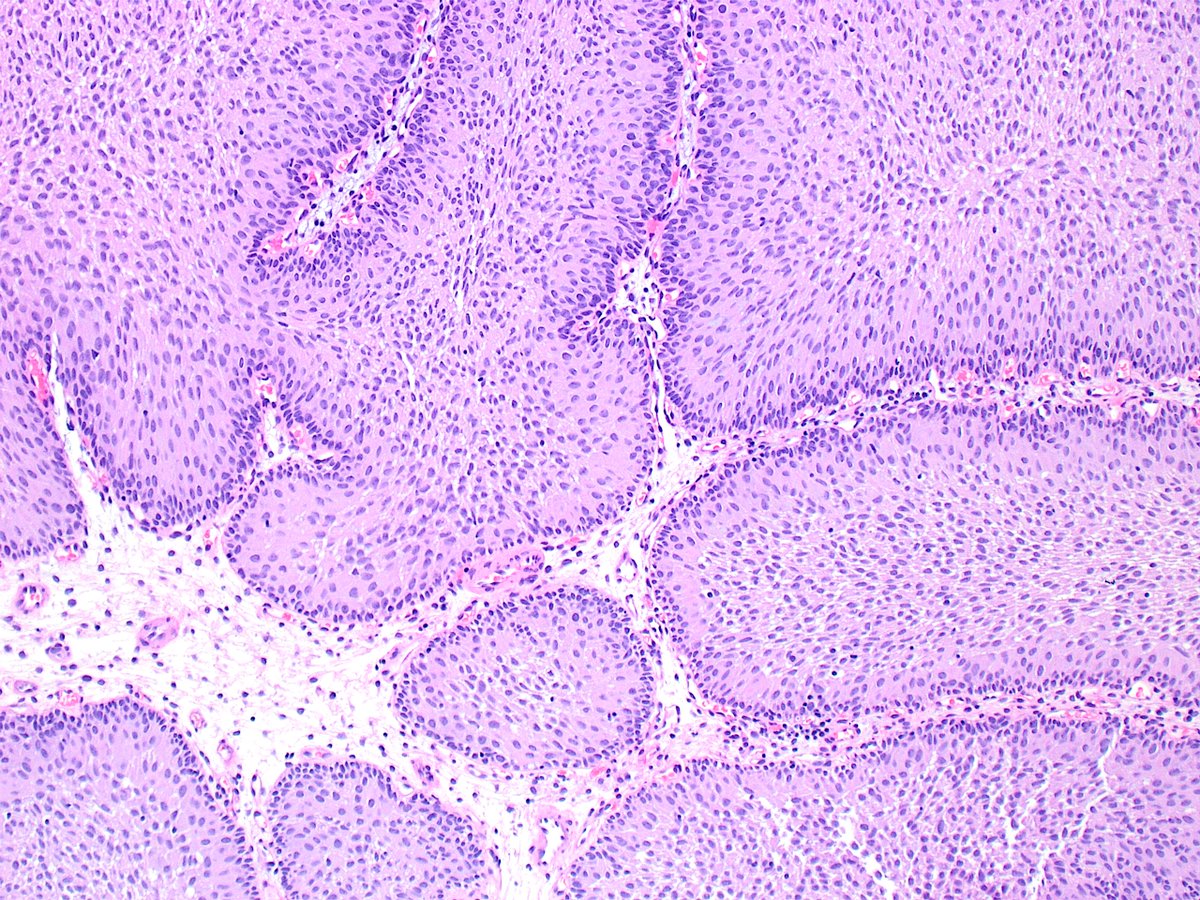

@BenjaminAwood Reviewed a case in 2014 of basal cell carcinosarcoma. Sarcomatous component initially missed & recurred (dx'ed as sarcoma) -> mets -> death